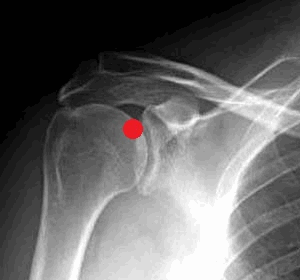

Передне-задняя артрограмма плеча, ротированного кнаружи: визуализируется нормальный косой контур прикрепления капсулы к анатомической шейке плечевой кости. Распространение контраста латеральнее данной линии и/или латеральнее большого бугорка указывает на разрыв вращательной манжеты. Обратите внимание на нормальное заполнение кармана двуглавой мышцы и подмышечного кармана. Передне-задняя артрограмма плеча, ротированного внутрь: визуализируется контраст, заполняющий подлопаточный карман. Подлопаточный карман (иначе называемый сумкой) образует сумку, перекидывающуюся через верхний край подлопаточной мышцы. Свободные тела часто мигрируют в нее или в подмышечный карман. Рисунок, вид спереди: показаны взаимоотношения мышц-вращателей плеча и интервала вращателей—участка треугольной формы, расширяющегося медиально и сужающегося латерально, с вершиной у переднего края большого бугорка. Показано сагиттальное сечение внутрисуставной части области плеча, удалена головка плечевой кости. Верхняя и средняя суставно-плечевая связки берут свое начало рядом с сухожилием двуглавой мыщцы, но верхняя суставно-плечевая связка имеет горизонтальное направление и образует часть петли сухожилия двуглавой мышцы. Средняя суставно-плечевая связка имеет косое нижнелатеральное направление и обеспечивает стабильность передней части. Пучки нижней суставно-плечевой связки берут свое начало около экватора суставной впадины лопатки спереди и сзади и образуют переднюю и заднюю границы подмышечного кармана. Схематично оказана нормальная анатомия интервала вращателей. Поперечные сечения в латеральной, средней и медиальной частях интервала вращателей представлены вдоль нижней части изображения. У латеральной части интервала, сразу проксимальнее входа в межбугорковую борозду плечевой кости, медиальный пучок клювовидно-плечевой связки (голубой цвет) и верхняя суставно-плечевая связка образуют петлю вокруг сухожилия длинной головки двуглавой мышцы. В средней части интервала вращателей клювовидно-плечевая связка покрывает верхнюю поверхность сухожилия двуглавой мышцы, а верхняя суставно-плечевая связка образует Т-образное соединение с клювовидно-плечевой связкой. Около медиального края интервала вращателей верхняя суставно-плечевая связка представляет собой округлую структуру, лежащую кпереди от сухожилия двуглавой мышцы; обе структуры покрыты U-образной клювовидно-плечевой связкой. Первая из шести выбранных косых корональных Т1ВИ МР-артрограмм, полученных вдоль оси сухожилия надостной мышцы. Задний пучок нижней суставно-плечевой связки образует толстый, четко различимый пучок по заднему краю подмышечного кармана. Задневерхняя губа суставной впадины лопатки часто имеет немного более высокую интенсивность сигнала, чем остальная часть, вероятно, вследствие артефакта «магического угла». Обратите внимание, что у этого пациента 20 лет в диафизе плечевой кости в первую очередь визуализируется кроветворный костный мозг, в то время как эпифиз содержит преимущественно желтый костный мозг. Очаги кроветворного костного мозга в диафизе плечевой кости сохраняются на протяжении всей жизни и могут быть ошибочно приняты за патологическое замещение. Кзади от начала двуглавой мышцы верхняя губа плотно прилежит к нижележащему суставному хрящу. Подмышечный карман четко очерчен и выступает за нижний край суставной впадины лопатки к шейке плечевой кости. Двуглавая мышца берет свое начало у надсуставного бугорка лопатки и крепится к верхней губе, затем следует латерально и кпереди над головкой плечевой кости и входите межбугорковую борозду плечевой кости. Визуализация места прикрепления длинной головки двуглавой мышцы плеча к суставной губе может различаться в зависимости от ротации плеча. В этом случае плечо ротировано кнаружи и проксимальная часть двуглавой мышцы располагается практически параллельно к плоскости визуализации. Трехстороннее отверстие визуализируется между сухожилием двуглавой мышцы и верхней губой. Эту находку кпереди от места прикрепления длинной головки двуглавой мышцы плеча к суставной губе не следует путать с повреждением верхней суставной губы лопатки спереди назад. Обратите внимание на нормальное распределение внутрисуставного контраста вдоль влагалища сухожилия двуглавой мышцы. Как правило, в передней проекции сустава визуализируется подлопаточный карман, выступающий над верхним краем подлопаточной мышцы. Обратите внимание на нормальное соединение сухожилия подлопаточной мышцы и самой мышцы. Также визуализируется наиболее передняя часть клювовидно-плечевой связки, сливающаяся с латеральными волокнами подлопаточной мышцы. На первой из шести отобранных Т1 FS МР-артрограмм визуализируется плечевой сустав в направлении сверху вниз. Сухожилие двуглавой мышцы проходит над головкой плечевой кости. Клювовидно-суставная связка визуализируется частично, сплетаясь с клювовидно-плечевой связкой. Клювовидно-плечевая связка имеет средний пучок, который образует часть петли сухожилия двуглавой мышцы, и латеральный пучок, который перекидывается через передний край подлопаточной мышцы и крепится к подлопаточной мышце, а также к малому и большому бугоркам, формируя таким образом часть поперечной связки. В литературе обсуждается вопрос, является ли поперечная связка самостоятельной структурой. Она представляет собой слияние волокон подлопаточной мышцы и петли сухожилия двуглавой мышцы, удерживает сухожилие двуглавой мышцы в межбугорковой борозде. Передняя и задняя губы прилежат к хрящу на передней поверхности суставной впадины. Задняя губа не имеет сублабральной борозды и жидкость между суставным хрящом и губой всегда наблюдается в норме. Средняя суставно-плечевая связка прилежит к заднему краю сухожилия подлопаточной мышцы, с которым сливается в нижней части. Площадка истонченного хряща суставной впадины лопатки в норме расположена центрально и известна как «голая зона». Здесь часто располагаются выступающие кровеносные сосуды кзади от головки плечевой кости, которые иногда ошибочно принимают за субхондральные кисты. Анализ округлых участков на последовательных снимках поможет установить их тубулярное строение, что соответствует сосудистым структурам. При визуализации места прикрепления передней части капсулы сустава к лопатке отмечается значительная вариабельность. В норме в данной области глубже подлопаточной мышцы наблюдается небольшой карман. Подмышечная петля состоит из множества пучков с участками небольшого расхождения между ними. Это создает слоистый вид в месте их прикрепления к шейке плечевой кости. Обратите внимание, что хотя верхняя часть подлопаточной мышцы фиксирована к плечу посредством сухожилия, нижняя-крепится посредством мышечной ткани. Первая из девяти отобранных сагиттальных PD FS МР-артрограмм, от латеральной к медиальной: визуализируется нормальная вращательная манжета в виде кольца по типу велосипедной шины вокруг верхней и задней поверхностей головки плечевой кости. Небольшие разрывы сухожилия надостной мышцы часто возникают в переднем или «ведущем» крае, который лучше визуализируется в сагиттальной проекции. Обратите внимание на высокоинтенсивный сигнал в области дельтовидной мышцы, отражающий наличие лидокаина, введенного во время процедуры. Последовательность PD FS позволяет визуализировать контрастное вещество и другие жидкости с высокоинтенсивным сигналом. Визуализируется подлопаточная мышца, которая прикрепляется к малому бугорку. Сухожилие двуглавой мышцы находится сразу выше данного участка при изгибе и вступлении в межбугорковую борозду. Клювовидно-плечевая связка лежит выше двуглавой; она и поверхностные волокна подлопаточной мышцы сливаются, образуя поперечную связку межбугорковой борозды. Сагиттальная плоскость лучше подходит для оценки внутрисуставного расположения сухожилия двуглавой мышцы, поскольку эффект частичного объема затрудняет точную визуализацию в корональной и аксиальной плоскостях. Обратите внимание, что подлопаточная мышца имеет множественные сухожильные волокна, чередующиеся с мышечными, а нижняя треть- мышечное прикрепление к малому бугорку. На этом уровне начинает визуализироваться подлопаточный карман, простирающийся над верхним краем подлопаточной мышцы. Передний и задний пучки нижней суставно-плечевой связки определяются в месте прикрепления к хирургической шейке плечевой кости. Клювовидно-плечевая связка представлена широким пластом и делится на медиальный и латеральный пучки. Подмышечный карман имеет множество пучков, что создает исчерченный вид. Клювовидно-плечевая связка заполняет интервал вращателей и перекидывается через верхнюю часть сухожилия двуглавой мышцы. Латеральный пучок визуализируется в месте прикрепления к переднему краю подлопаточной мышцы. Клювовидно-плечевая связка и клювовидно-суставной пучок визуализируются в месте их начала у основания клювовидного отростка. Их визуализация в значительной степени вариабельна. В норме визуализируются множественные карманы сустава: подмышечный, задний и подлопаточный (часто именуемый подлопаточной сумкой). Снимок получен медиальнее предыдущего, но у другого пациента; вследствие большего растяжения полости сустава достигнута лучшая визуализация карманов сустава и суставно-плечевых связок. Суставная губа визуализируется частично. Хотя сагиттальный срез не является первостепенным для оценки губы, на этом уровне наличие контрастного вещества между костью и губой подтверждает разрыв губы. На аксиальной Т1 МР-артрограмме визуализируется сублабральное окно. Этот вариант нормы имеет место в передневерхнем квадранте губы, где редко возникают изолированные разрывы губы. Они не распространяются ниже уровня клювовидного отростка. В отличие от неровного зазубренного контура при разрыве губы, сублабральное окно имеет ровный контур. На аксиальной Т1 МР-артрограмме визуализируется сублабральное окно (другой пациент). Снимки получены ниже для дифференцировки между губой и сублабральным окном (в этом случае верхняя губа присоединяется к кости более низко) или комплексом Буфорда (в этом случае тяжистая средняя суставно-плечевая связка сливается с подлопаточной мышцей и отдельная верхняя губа визуализируется более низко). Артроскопия: визуализируется прочно прикрепленная суставная губа кзади от места прикрепления длинной головки двуглавой мышцы плеча к суставной губе и сублабральное окно в передневерхнем квадранте сустава. На рисунке в сагиттальной плоскости показан комплекс Буфорда: передняя верхняя суставная губа отсутствует, средняя суставно-плечевая связка утолщена и натянута. На аксиальной Т1 FS МР-артрограмме визуализируется комплекс Буфорда. Средняя суставно-плечевая связка утолщена и натянута. Такое строение может быть немного нестабильным, так как пациенты с комплексом Буфорда имеют повышенный риск повреждения верхней суставной губы лопатки спереди назад. На аксиальной Т1 FS МР-артрограмме у пациента с комплексом Буфорда на этом уровне определяется наличие губы, средняя суставно-плечевая связка остается натянутой.